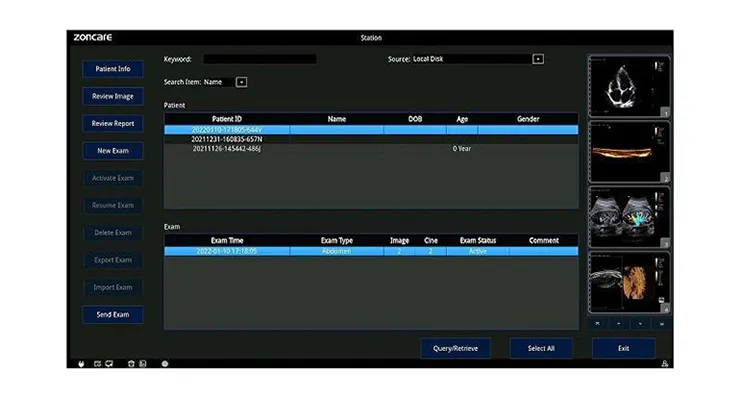

- ведение базы данных исследований животных

- автоматическое формирование отчета по проведенным исследованиям

- печать отчета, экспорт отчета на USB, DICOM-сервер